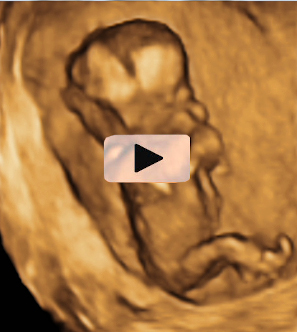

En la semana 12 de gestación, la embarazada aún no nota los movimientos del bebé que crece dentro de su útero. Pero en esta ecografía en 4D se observa sus vigorosos movimientos.

Ecografía 4D de feto de 12 semanas de espaldas

La curiosa ecografía de este feto de 12 semanas comienza con la imagen de espaldas. El niño se gira hasta colocarse de perfil y es entonces cuando empieza a mover brazos y piernas con agilidad. Todo un signo de bienestar fetal.